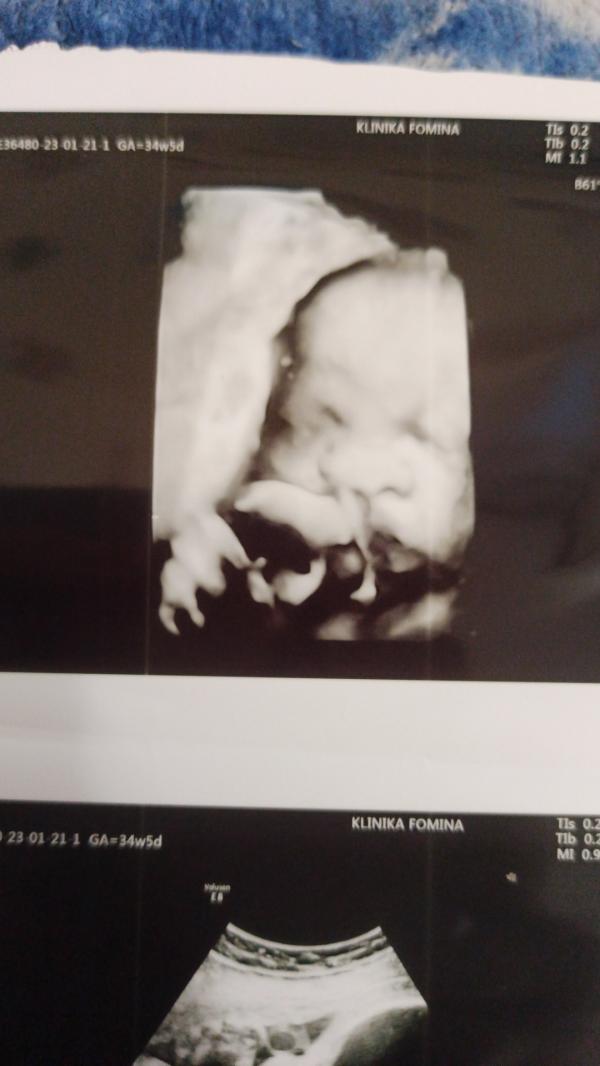

т и сегодня началась 35-36 неделя🥰совсем чуть-чуть и мы увидемся с моей кнопочкой 🥰 25 скрининг, потом сразу приём гинеколога, 26 когда, сегодня сдала 5 флакончиков крови 🤦♀️😤чувствую себя нормально, не считая запора 😤21 была на УЗИ сказали что всё хорошо, малышка весит 2,400. Только плацента старая, это потому что болею, сказали не чего страшного, кровопоток хороший, 25 будем слушать скрининг.... Выделение белые, слизистые... Ночью сплю отвратительно 😫днём высыпаюсь..... К появлению малышки всё готова 🥰